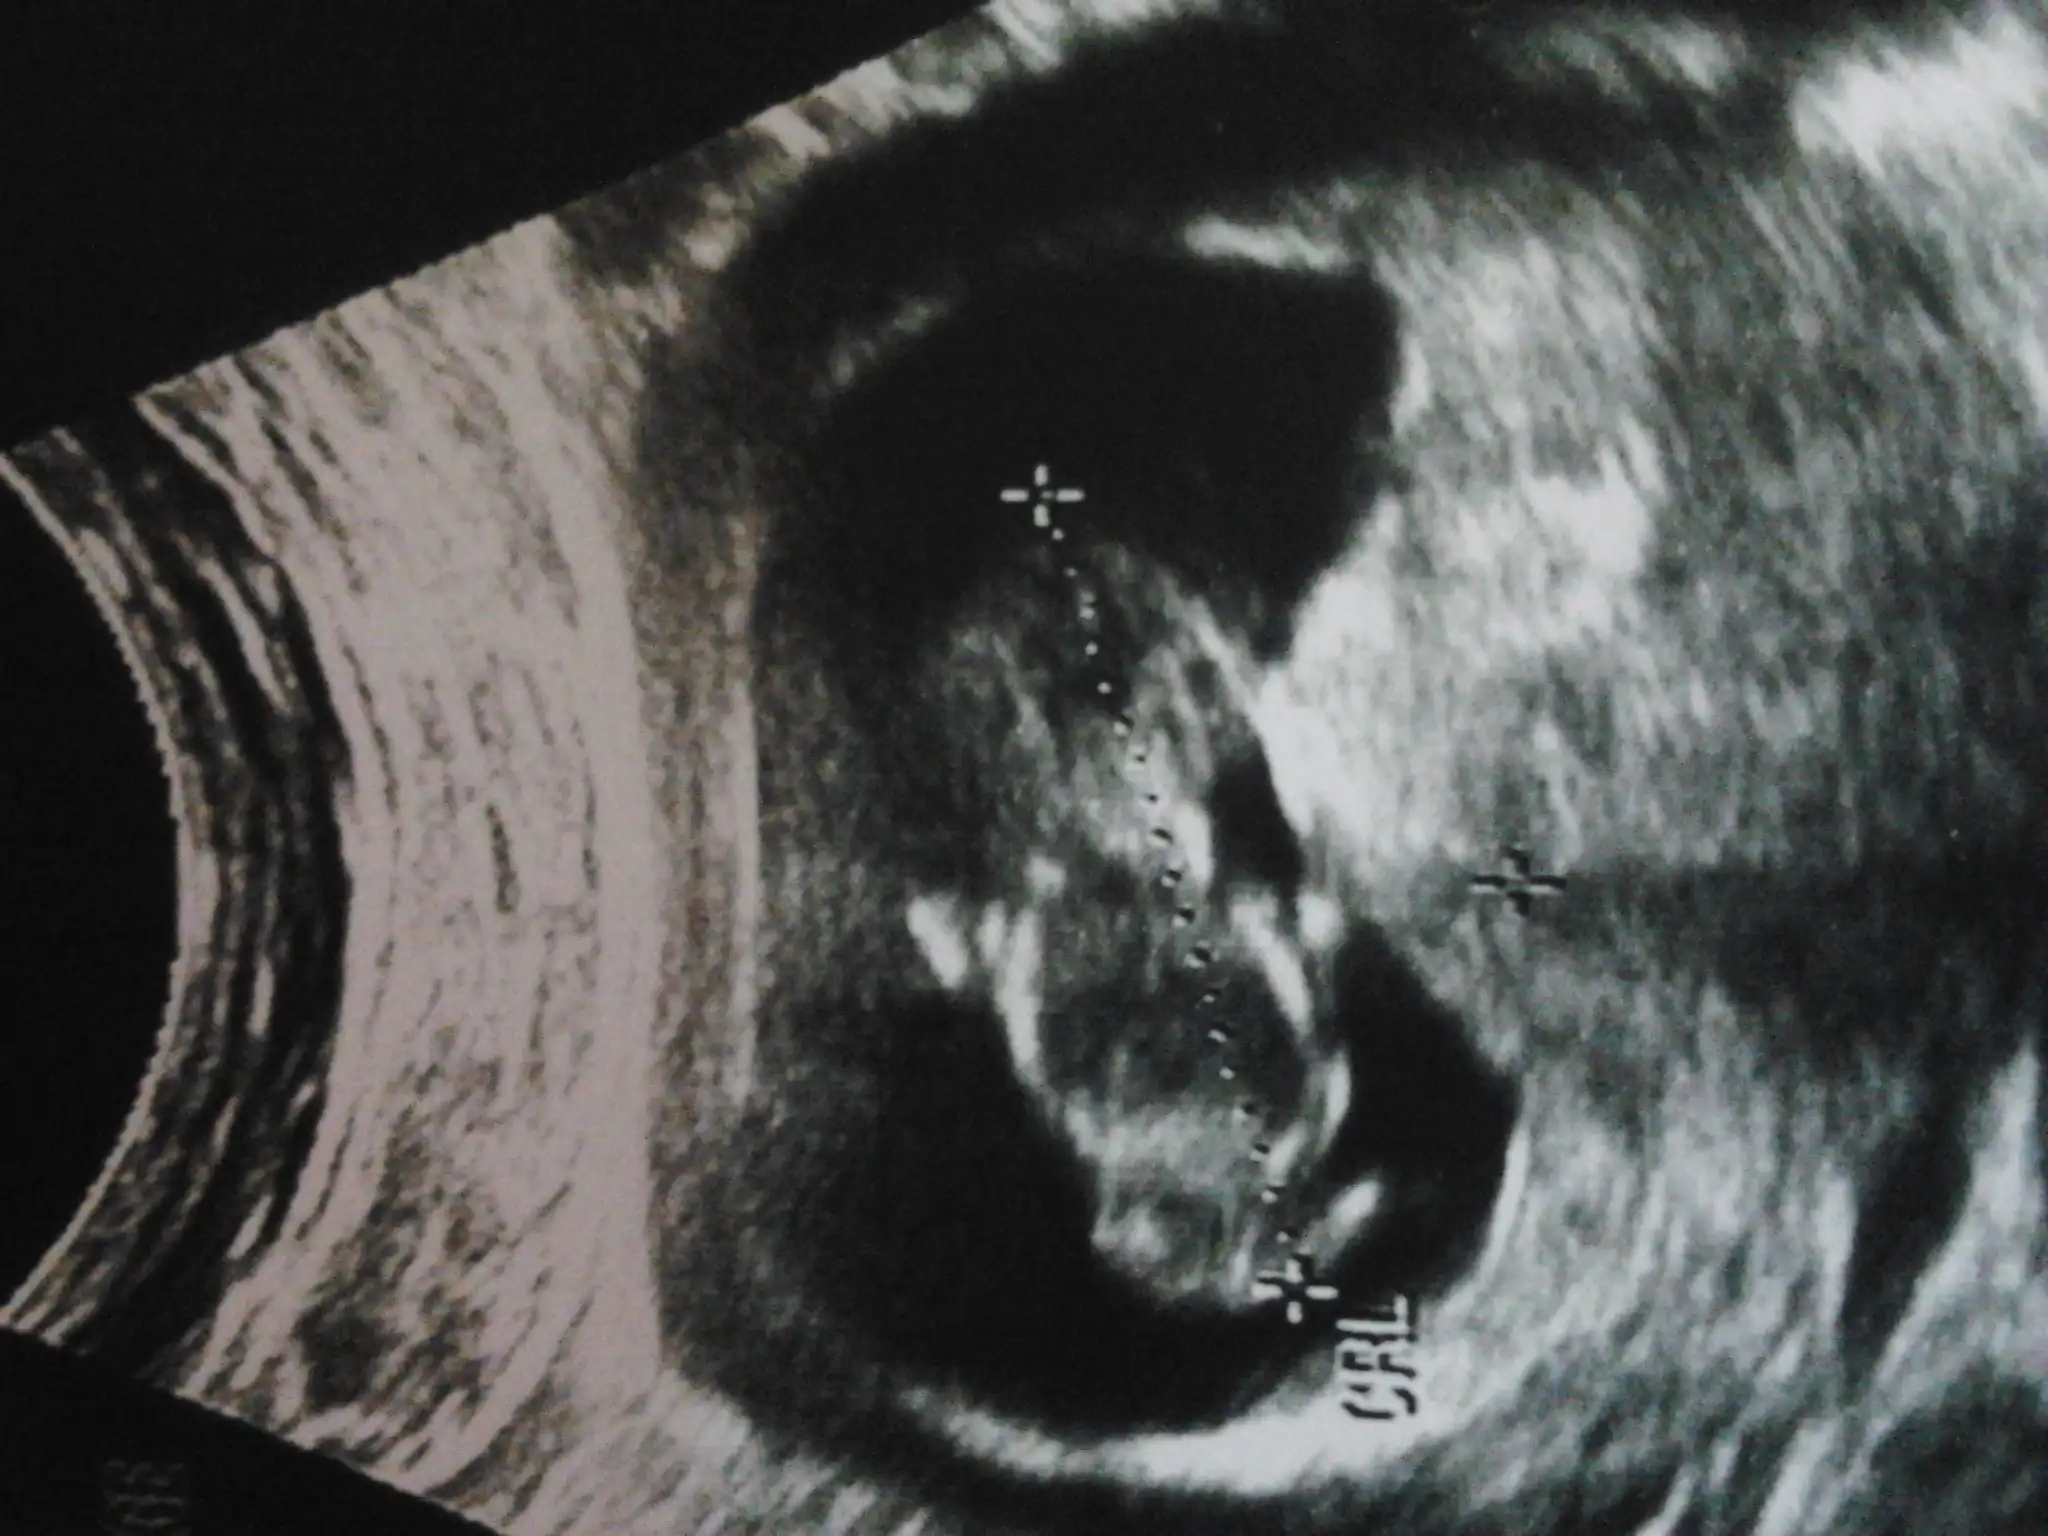

nub için kötü bi pozisyon ama kıza benzettim benKızlar bizde dün 12+0a girdik. Çok merak ediyorum cinsiyetimizi ama dr birşey soylemedi biran önce ogrensekte öyle hitap etsek yavrumuza :) sizce tahminen nedir :)Eki Görüntüle 1260145

kız gibi net görünmüyor amaEki Görüntüle 1262219